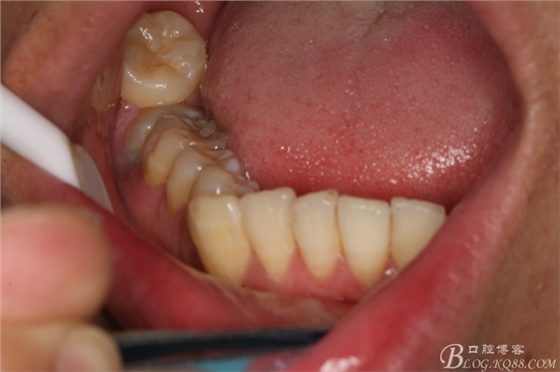

圖4.患者的口內(nèi)影像檢查:右側(cè)47萌出少,合向脫位間隙亞種不足